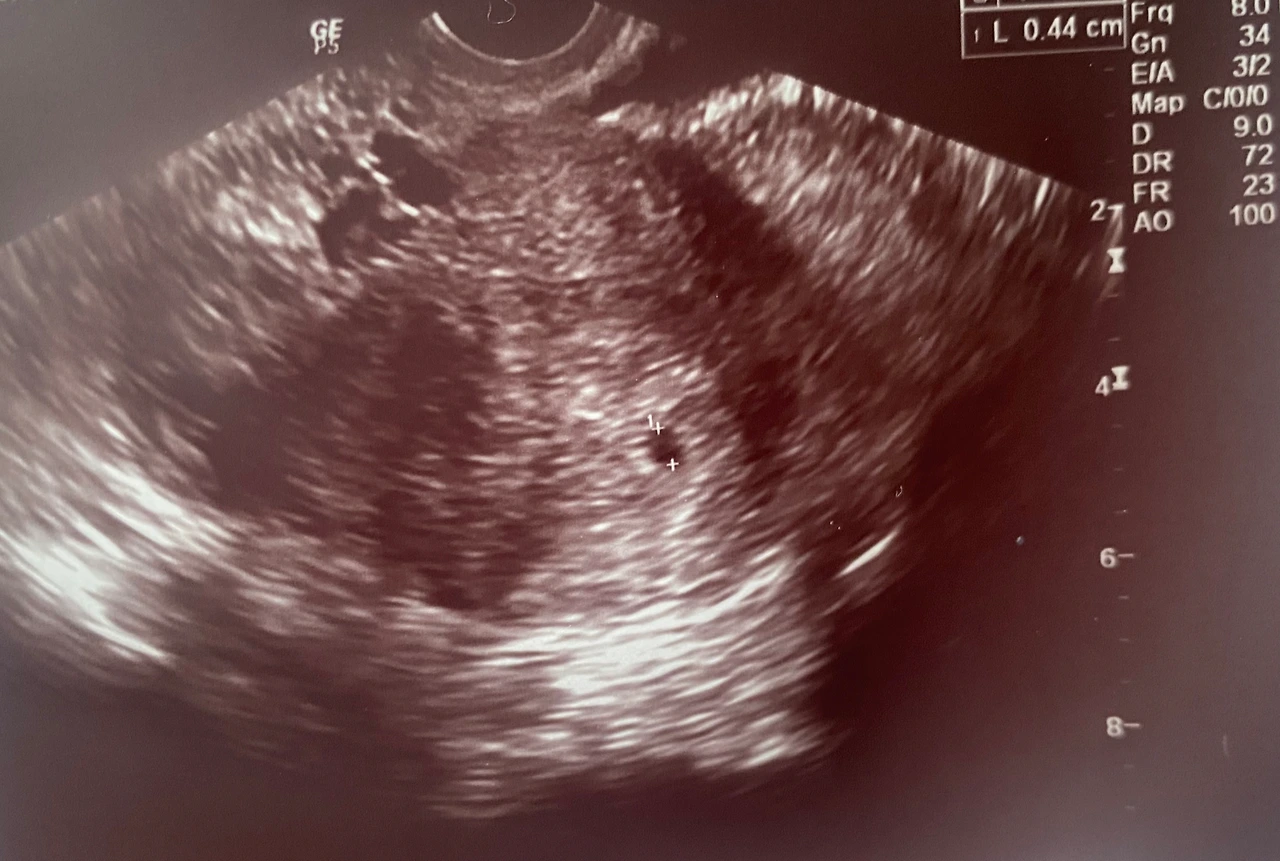

작고 소중한 0.44cm 짜리의 아기집

이론상(?) 4주 4일이 되던 수요일 오후. 가까운 산부인과로 가서 0.4cm정도의 작고 동그랗게 생긴 아기집을 확인할 수 있었다. 이것으로 임신이 확실해졌다! 그 후 바로 엄마에게 전화해 이 사실을 알렸다. 한글날까지 기다리고 집에 가서 직접 얼굴을 보고 깜짝 임밍아웃을 하기에는 성질이 급해서 참을 수가 없었다. 전화로 소식을 전하니 엄마는 너무나 기뻐하셨다.

아무튼 아기집만 확인하면 맘 편하게 임신이구나 할 줄 알았다. 그런데 막상 확인된 아기집의 크기가 너무 작지는 않은 건지, 아직 난황(탯줄이 생기기 전 배아에게 영양분을 공급하는 기관)은 보이지 않는데 다음 주엔 난황이 자랄지, 그동안 갑자기 피가 나오거나 배가 아프진 않을지 걱정이 되었다. 임신테스트기 2줄만 나오면 임신인 줄 알았는데 통과해야 할 단계가 한두 개가 아니었다. 건강한 아이가 태어나는 것은 수 개의 모든 경우의 수를 통과한 '기적' 그 자체였다.